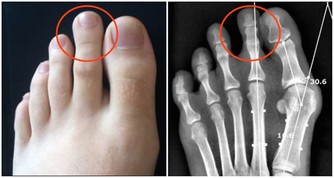

保險起見,他決定找了另一位醫生協助,才發現他腳上的紅色痕跡根本不是血管,是巨大的蠕蟲!

蠕蟲時常會藉由貓狗的排泄物傳染,是一種寄生蟲疾病。

醫生也評斷男子可能是赤腳踩在地板上,才感染到這樣的寄生蟲。